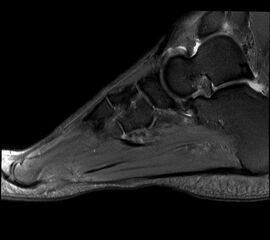

Abbildung 1: Plantarer und dorsaler Sporn im Röntgenbild und im MRT

Abb. 1a und Abb. 1b: großer dorsaler Fersensporn und ein minimaler plantarer Sporn, Patient, 50 Jahre.

Abb. 1c: Bild eines isolierten großen plantaren Fersensporns. Patientin, 32 Jahre.

Zum Lesen der Bildbeschreibung und zur Vollansicht bitte die Bilder anklicken. Bilder: Manfred Thomas.

Dorsaler Fersensporn: Dorsale Fersenschmerzen können auch durch einen echten dorsalen Fersensporn entstehen (siehe Abb. 1). Dieser entsteht als knöcherne Ausziehung durch Verkalkung der Achillessehne an ihrem Ansatz.